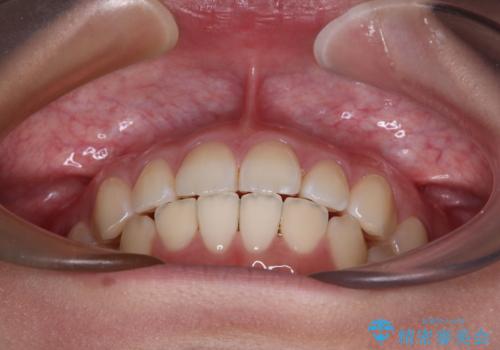

1年弱の短期間で、望み通りのスッキリとした口元に仕上げることができました。